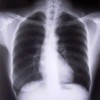

Infants who live in “moldy” homes are three times more likely to develop asthma by age 7 — an age that children can be accurately diagnosed with the condition. Study results are published in the August issue of Annals of Allergy, Asthma & Immunology, the scientific journal of the American College of Allergy, Asthma and Immunology […]